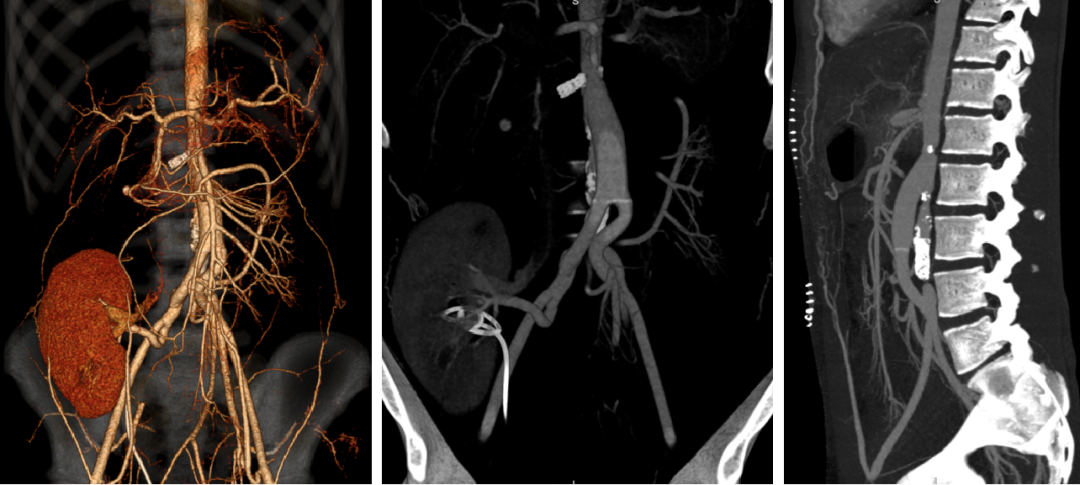

06

EVAR术后Ia内漏

女性,82岁

体检发现腹主动脉瘤,外院于2018年12月行EVAR术,术后一年,自觉出现腹部搏动性包块,于2020年6月到我院就诊,发现Ia内漏

一般状况较差,高血压,冠心病PCI病史

手术方案:

Plan A 开放手术:胸腹联合切口,行动脉瘤切除人工血管置换+全内脏动脉重建

创伤大,手术时间长;患者高龄,心肺功能差,恐难以耐受

Plan B 介入手术:

近端cuff支架植入:裸支架贴壁不良,内部放cuff无法贴壁密封

动脉瘤腔内修复+内脏动脉腔内重建,如何重建?

开窗或分支支架:内脏区成角大,且有裸支架干扰,重建难度极大,且容易内漏

烟囱:左肾、SMA适合,但右肾开口成角大,超选进入困难,且烟囱支架极易闭塞,如何解决?

最终选择Plan C 杂交手术:动脉瘤腔内修复+左肾动脉、肠系膜上动脉烟囱支架重建+右肾自体肾移植

很好弥补了单纯介入手术的缺点,降低了手术风险,提高了手术成功率

左侧卧位,右侧肋缘下切口,取右肾,保存于灌注液中。将右肾移植于右侧髂窝,右肾动静脉吻合于右侧髂外动静脉

术后5天复查CT

近端I型内漏完全消失

烟囱支架通畅

移植肾显影良好